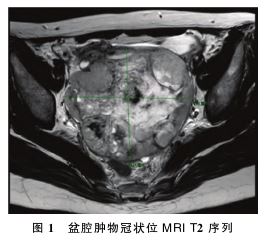

:子宫右后方可扪及直径约12 cm囊实性包块,与直肠关系密切,向右侧盆壁延伸。盆腔磁共振成像

(MRI)检查示:盆腔见一团片状长T1长T2信号影,大小约12 cm×10 cm×12 cm,中央伴坏死囊变及出血,实性成分弥散受限,表观扩散系数(ADC)减低,增强扫描实性成分明显强化,右侧附件来源恶性肿瘤可能,生殖源性肿瘤可能(卵黄囊瘤?无性细胞瘤?),上皮源性肿瘤可能;直肠左前缘腹膜结节软组织影,约1.1 cm,转移可能;左侧附件区囊腺瘤可能,大小约1.5 cm×3.9 cm;盆腔少许积液。见图1。

2.1 临床特征 卵巢SMARCA4缺失性未分化肉瘤在临床上十分罕见。疾病缺乏特异性的临床表现,该患者主要表现为双侧卵巢巨大囊实性肿块,伴有腹痛及反复发热。因肿瘤体积较大,且引起腹水的产生,常伴有压迫症状,例如腹胀、尿频等。盆腔MRI常表现为长T1长T2信号影,因肿瘤体积大,中央可伴坏死囊变及出血,实性成分弥散受限,ADC减低,增强扫描实性成分明显强化。超声表现为不均质低回声,内可见液性暗区,可探及丰富血流信号。肿瘤指标可见CA125上升,而其余HE4、AFP、CEA、CA724、CA199均在正常范围内。